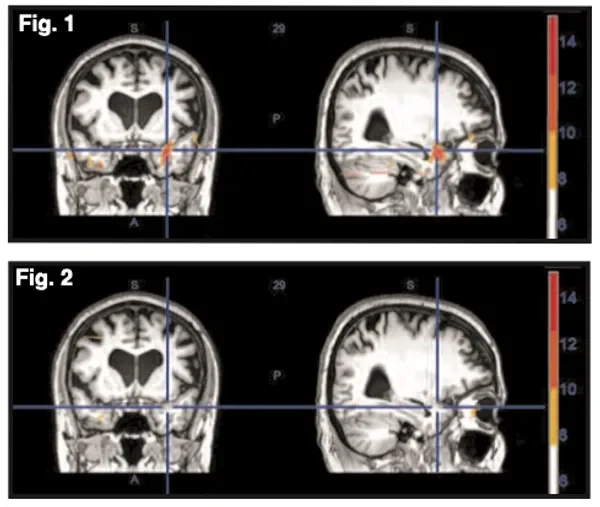

Before & After: NET’s Impact on the Brain’s Stress Center

There is now quantifiable evidence as to ‘why’ patients feel better when treated with NET, and the dramatic pre- and post- treatment changes can be seen in fMRI brain images.

A recently published study examined the effects of NET on brain physiology in patients experiencing stress symptoms.